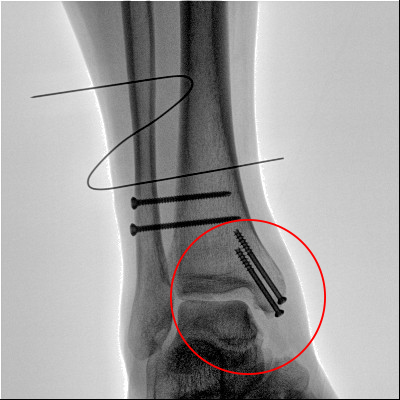

踝關(guān)節(jié)骨折在X影像上的表現(xiàn)有很多種。如內(nèi)踝骨折和外踝骨折,我們可以在影像上看到骨折處的骨折線是不連續(xù)的。還有后踝的骨折,內(nèi)踝、外踝、后踝聯(lián)合在一起發(fā)生的骨折,我們稱之為“三踝骨折”,這些都是在X影像上能夠顯示出來的。

內(nèi)踝骨折

外踝骨折

后踝骨折

三踝骨折